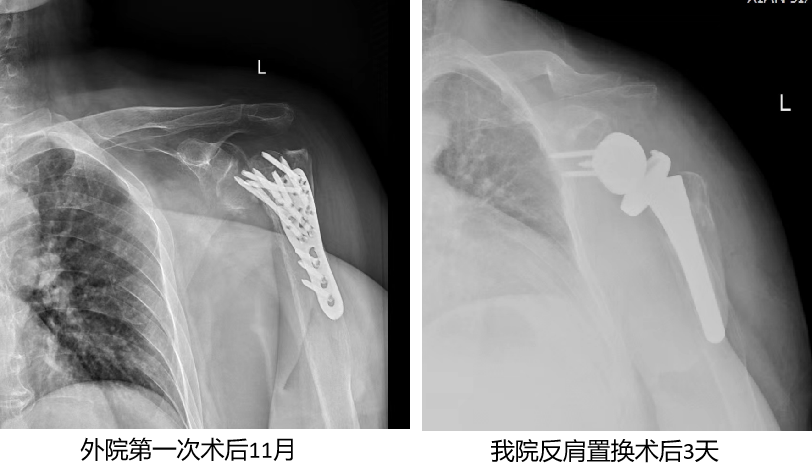

李阿姨在11个月前因受伤导致左肱骨近端粉碎性骨折并伴随左肩关节活动障碍。在外院接受了切开复位内固定手术后,由于同时患有骨质疏松,术后左肱骨近端骨折愈合情况不佳,肱骨头逐渐坏死并被吸收。这一连串的不幸让李阿姨的左肩反复承受剧烈的疼痛,日常活动也受到了极大的限制。疼痛不仅影响了她的睡眠,使她时常在夜间痛醒,更使她的日常生活,如梳头、穿衣、进食等变得异常艰难。李阿姨和家人辗转多家三甲医院寻求治疗,但由于病情复杂,一直未能获得理想的疗效。

在手术过程中,凭借丰富的手术经验和精准的操作技巧,团队成功克服了多重困难。患者肩关节周围的软组织严重粘连、术野显露困难,加之肱骨头坏死、骨质疏松等棘手问题,都给手术带来了极大的挑战。此外,由于患者原有的肩袖组织等肩关节动力结构已丧失功能,团队需要巧妙利用周围其他肌肉组织来重建肩关节的稳定性和活动功能。在麻醉科和手术室团队的紧密配合下,反式肩关节置换术最终得以顺利完成。

术后李阿姨的肩部疼痛得到了显著缓解,经过康复科个性化的康复训练支持,李阿姨恢复迅速顺利出院。如今,她已能够自如地活动左肩,生活质量得到了极大提升,她对术后效果表示非常满意,感激之情溢于言表。反肩置换手术的成功实施,不仅让李阿姨肩膀重获新生,也展现了运动医学科在复杂肩关节疾病治疗领域的专业实力。